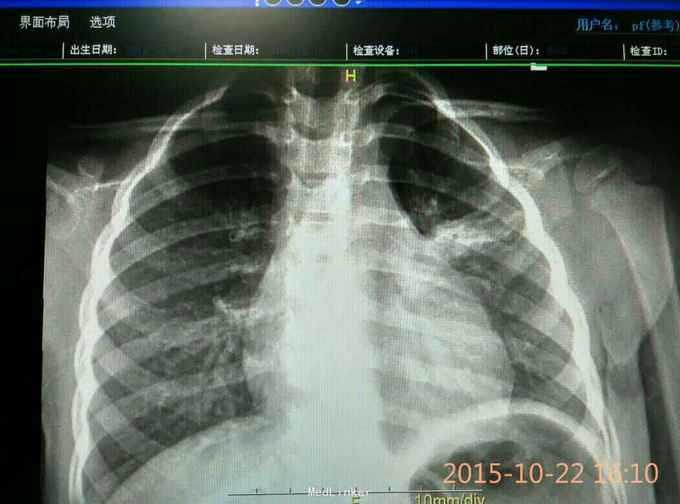

患儿,女,3岁 主诉:咳嗽5天,喘息2天 病史:患儿于5天前因受凉出现咳嗽,阵发性,有疾不易咳出,偶尔咳出黄痰。在外院检查:肺炎支原体阳性,CRP、均正常。静点阿奇霉素针3天,症状无减轻,并出现发热,咳嗽伴喘息。门診拍胸片以"肺炎"收住院。

体格检查:T,37.7℃,p:142次/分,R:25次/分,Bp:86/56mnHg,神志清,精神可,咽腔稍充血,双侧扁桃体无肿大,颈软,胸廓对称,无畸形,双肺呼吸音粗糙,可闻及痰鸣音,.心前区无异常隆起及凹陷,心尖搏动无弥散,听诊:心率:142次/分,各瓣膜无病理性杂音,神经系统未引出病理反射。化验:痰培养(-),MP-Ab(-),结明三项(-),ALP增高。CRP(-)血常规,胸片见图。

大叶性肺炎 治疗:抗感染::哌拉西林他唑巴坦加痰热清静脉点滴,止咳平喘对症处理活疗7天症状无改善且加重,调整为舒普森加阿奇霉素联合,佐以止咳平喘,匹多莫德,维生素AD等支持疗法,又治疗7天,症状体征消失痊愈出院。

该病人由于症状不典型,比如: 精神好,无明显发热,肺部听诊无啰音,血常规始终正常,CRP正常,MP-Ab(-),虽然胸片明显,因此仍按普通肺炎治疗,但无好转且加重。之后改用双联抗生素后症状迅速好转,二周痊愈。提示胸片检查的重要性,同时对大叶性肺炎双联抗感染的必要性,因为一些病原学检查会受外界因素影响而出现假阴性,如果只依赖化验检查而忽视临床表现则会而延误诊治。